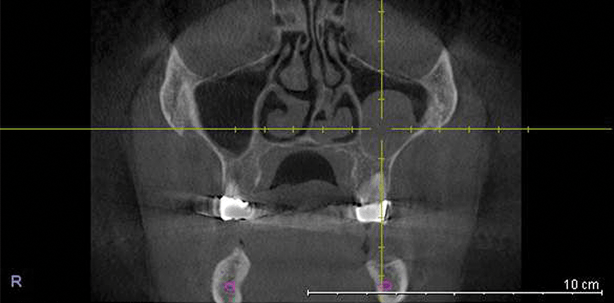

Es besteht allgemeiner Konsens, dass im seitlichen Oberkiefer bei reduziertem Knochenangebot eine dreidimensionale Diagnostik (DVT) notwendig ist. Darüber hinaus sollte bei einem geplanten Sinuslift nicht nur die Kieferhöhle, sondern auch das Siebbein vollumfänglich diagnostiziert werden können. Dies ist nur mithilfe eines DVTs mit großem Diagnostikfenster möglich.

Neben der Vermessung der Knochenstrukturen sind selbstverständlich alle im DVT erkennbaren Veränderungen zu erfassen und zu dokumentieren. Aus langjährigen (zwölf Jahre) Erfahrungen mit dem DVT wissen wir, dass in circa 40 Prozent aller untersuchten Fälle pathologische Befunde – meist ohne klinische Symptomatik – erkennbar sind.